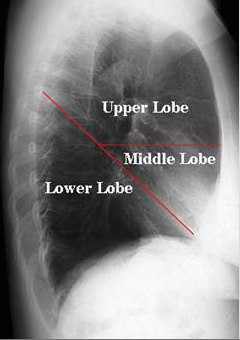

Представлена рентгенограмма правого лёгкого в боковой проекции с указанием топографии междолевых щелей.

В каждом лёгком различают доли, разделенные глубокими щелями. Правое лёгкое состоит из трёх долей, левое — из двух. На правую верхнюю долю приходится 20% лёгочной ткани, на среднюю — 8%, правую нижнюю — 25%, левую верхнюю — 23%, левую нижнюю — 24%.

Главные междолевые щели проецируются справа и слева одинаково — от уровня остистого отростка 3 грудного позвонка они направляются косо вниз и вперед и пересекают 6 ребро у места перехода его костной части в хрящевую.

Дополнительная междолевая щель правого лёгкого проецируется на грудную клетку по ходу 4 ребра от средней подмышечной линии до грудины.

На рисунке обозначены: Upper Lobe — верхняя доля, Middle Lobe — средняя доля, Lower Lobe — нижняя доля